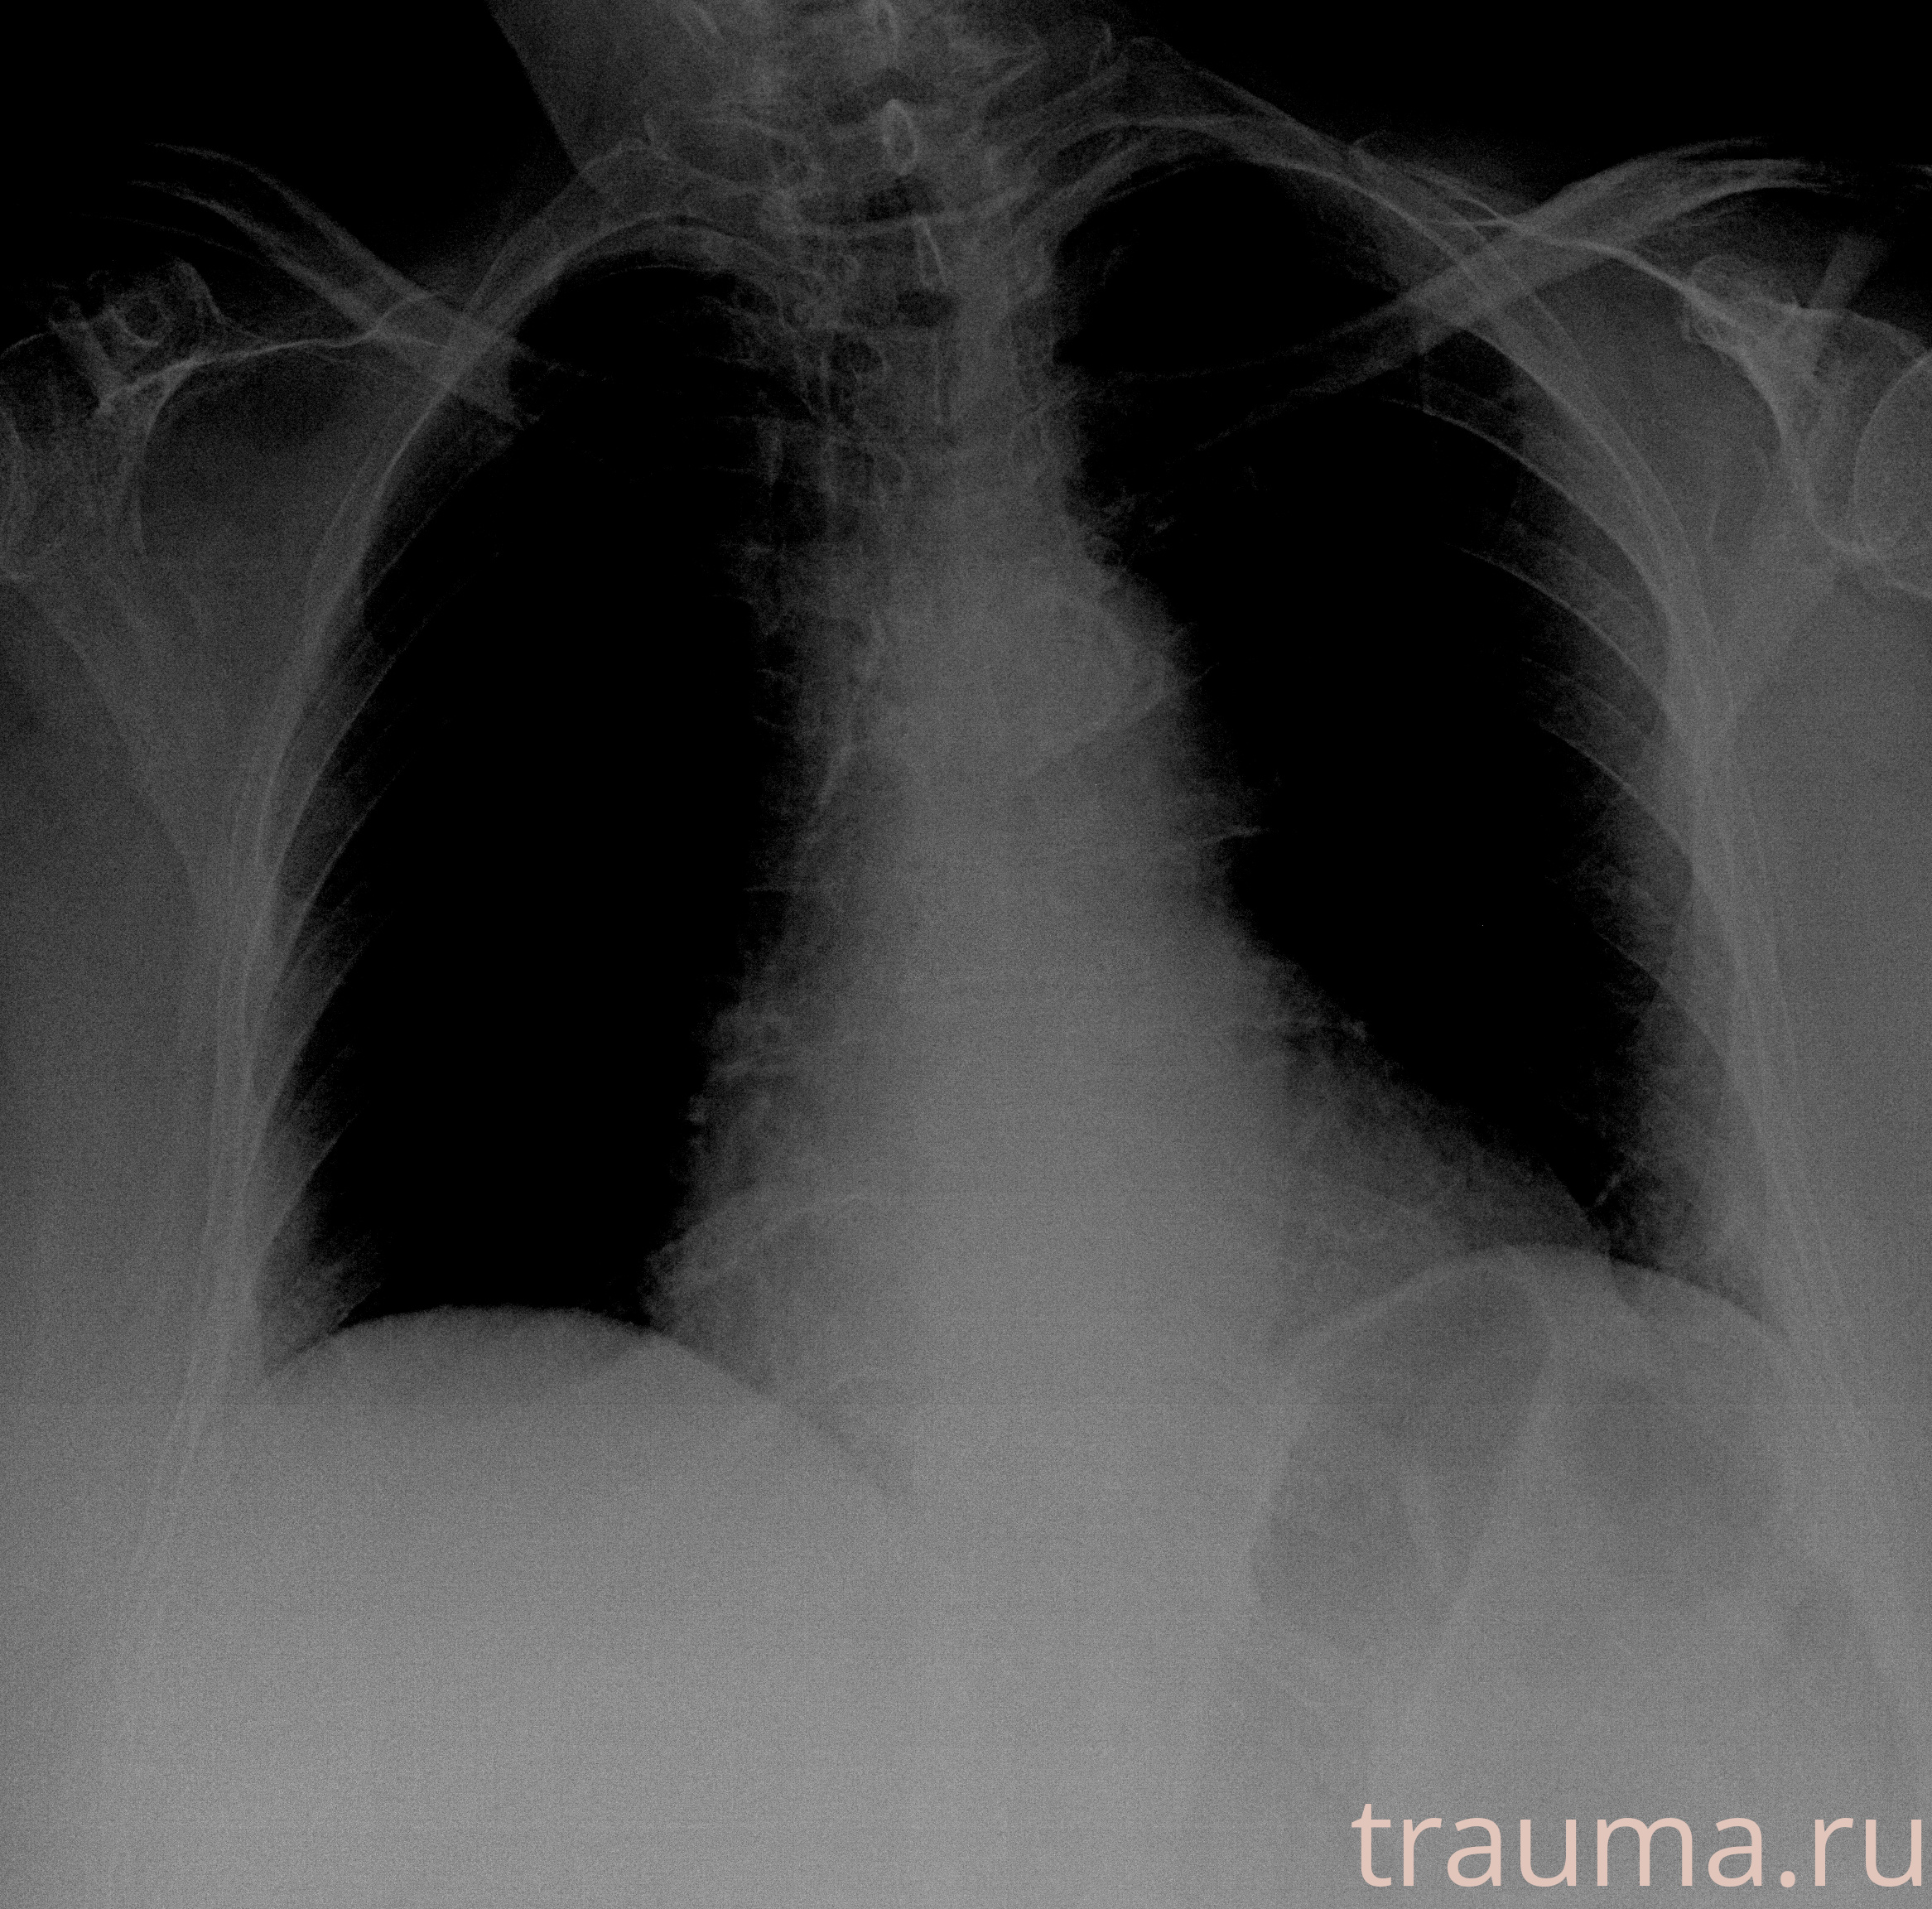

Рентгенограммы

Рентген на дому: по вашему адресу приезжает врач-рентгенолог, травматолог-ортопед с мобильным рентгеновским аппаратом, проводит диагностику травмы или заболевания, делает необходимые рентгенограммы, дает рекомендации по дальнейшему лечению. Получить качественные снимки в домашних условиях возможно благодаря уникальной методике, разработанной МосРентген Центром для института  Склифосовского